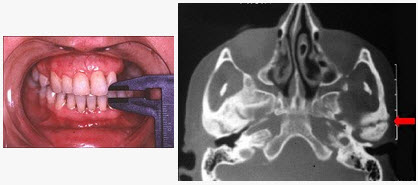

患儿,5岁,外伤后逐渐出现张口困难,咬合关系错乱,髁突动度减弱,外观及X线检查结果如图。最可能的诊断是()

A、上颌骨骨折

B、下颌骨骨折

C、颧骨骨折

D、颧弓骨折

E、颞下颌关节强直

E